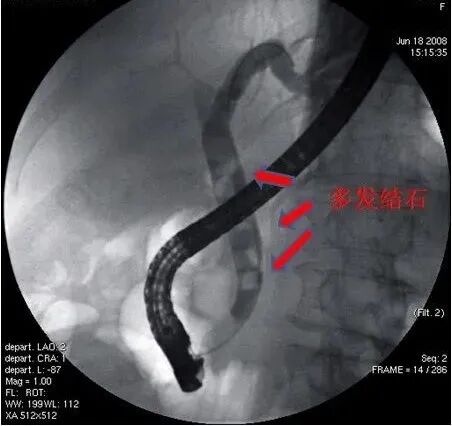

1.患者在介入手术室取左侧俯卧位,麻醉医师给予全身麻醉后,内镜医师通过十二指肠镜由口腔插至十二指肠乳头(胆总管开口),经乳头插入切开刀,注入造影剂,胆管显影,胆管内可见多发结石影。

2.对乳头进行小切开,扩张,利用取石网篮或取石球囊将结石逐个取出,冲洗胆道后再次造影,胆管内结石已清理干净,再根据病人情况决定是否需要留置鼻胆管或内支架引流。